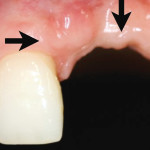

Preservazione dei livelli di tessuto molle con riabilitazione implantare provvisoria immediata

I dati attualmente disponibili indicano che impianti singoli con protesizzazione e applicazione immediate di corone provvisorie mostrano percentuali di successo comparabili a quelle di protocolli...